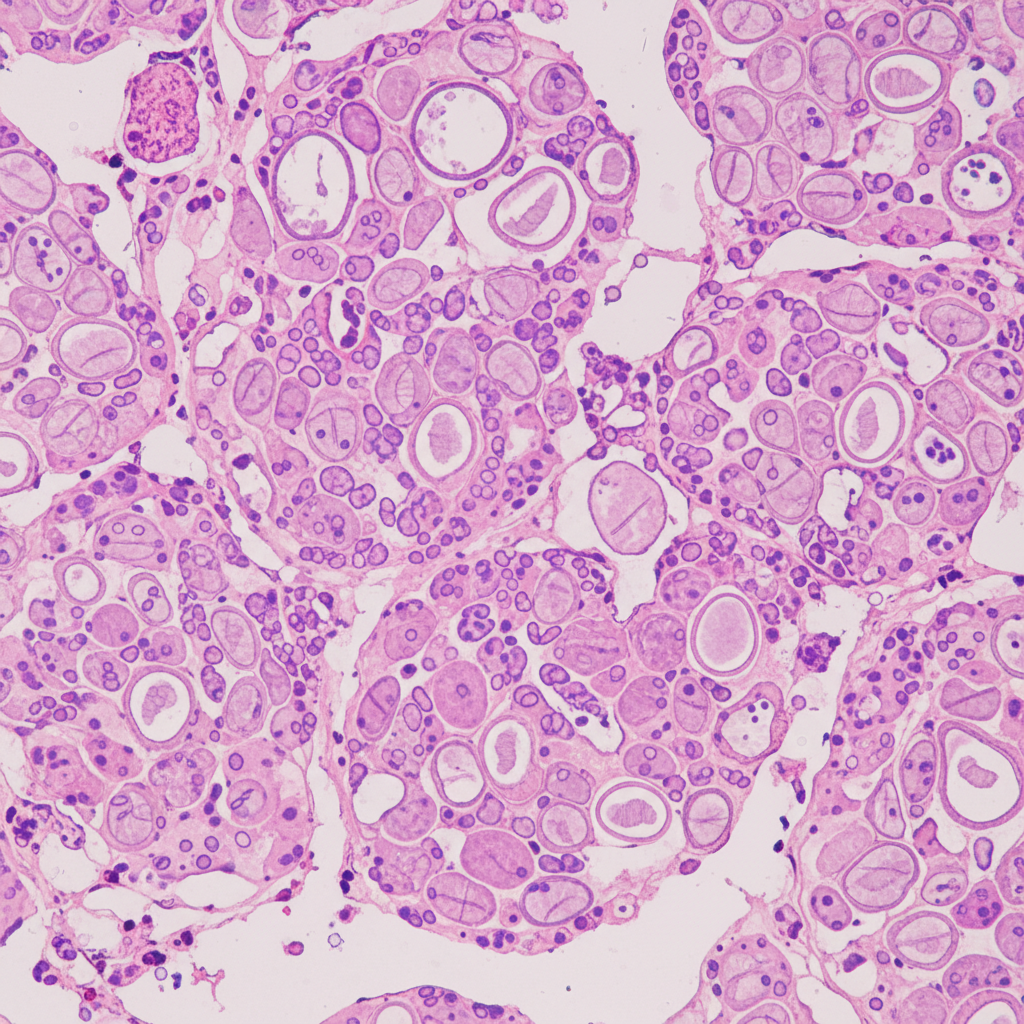

- 미세침흡인세포검사: 초음파로 의심스러운 결절을 발견했을 때 아주 가는 주사바늘로 조직 일부를 채취해서 현미경으로 암세포 유무를 확인하는 가장 중요한 확진 검사예요.약간의 불편함은 있지만, 대부분 큰 통증 없이 진행된답니다.